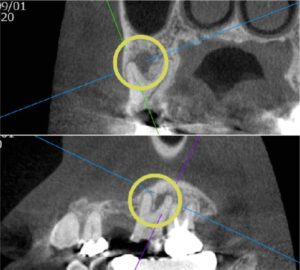

歯根分岐部病変に対する根管治療と外科的処置の併用症例

右上の歯ぐきの腫れを訴えて来院されました。 右上6番はレントゲン写真やCT撮影から、歯の神経および歯根の分岐部位に感染を起こしていることが…